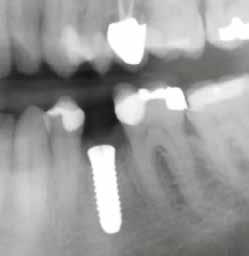

Mind a hat implantátum esetén kétlépcsős műtétet végeztünk. Minden sebészeti eljárást bódítás, illetve preoperatív szisztémás antibiotikus terápia nélkül végeztünk. A négy eset közül kettőnél leukocitában és vérlemezkében gazdag fibrint (L-PRF) alkalmaztunk a beavatkozás során (IntraSpin, BioHorizons; 2. táblázat). Minden esetben a pontos CERALOG menetvágási (maximum 15 ford./perc) és fúrási (maximális fúrási fordulatszám: 550–800 ford./perc) protokollt követtük. Az összes implantátumot manuálisan helyeztük be 35 Ncm maximális nyomatékkal. Az implantátumokba PEEK zárócsavar került (2. ábra). A lágyszövetet atraumatikus, felszívódó varrattal, szorosan zártuk/összevarrtuk. A műtétek után szövődmények nem jelentkeztek. A pácienseket arra kértük, hogy a műtét utáni héten naponta kétszer öblögessenek klórhexidinnel (PERIO-AID, 0,05%, DENTAID). Az alsó állcsontnál három hónapos, a felső állcsontnál öt hónapos gyógyulási időt vettünk figyelembe. Három hónap (1. eset) és öt hónap (2., 3. és 4. eset) elteltével a műtétek második stádiumát helyi érzéstelenítés mellett végeztük. A gyógyu-

lási csavarokat (PEEK titáncsavarral) maximum 15 Ncm-rel húztuk meg (3–6. ábra). Az összes implantátum kiváló stabilitást mutatott (a mérésekhez Periotestet használtunk, a Medizintechnik Gulden jóvoltából), és teljesen osszeointegrálódott. Ezt a radiológiai vizsgálatok is megerősítették.

3. a–b ábra: Röntgenfelvételek három hónap után (a) és a gyógyulási csavarok behelyezve (b, 1. eset).